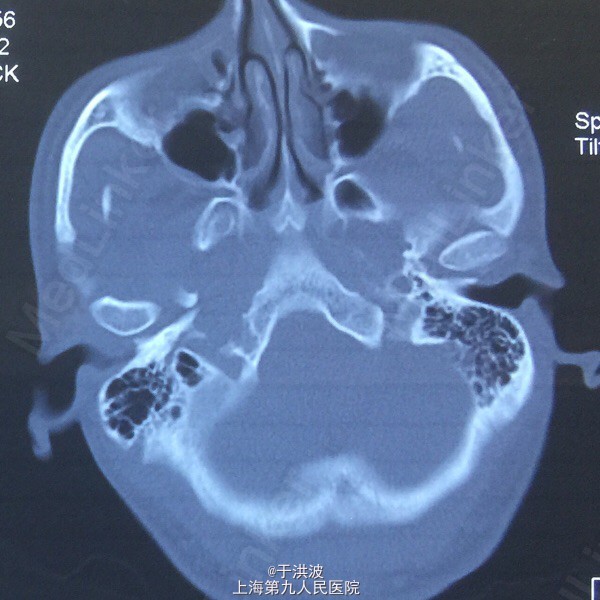

面部基本对称,右侧面部无明显膨胧,无压痛。口内右侧上颌前庭沟黏膜无异常,右侧上颌牙列松动,牙列上移,与下颌牙无咬合接触。CT示右侧上颌骨弥散性吸收。血常规未见异常

右侧上颌骨骨巨细胞瘤?坏死性肉芽肿? 局麻下行切取活检术